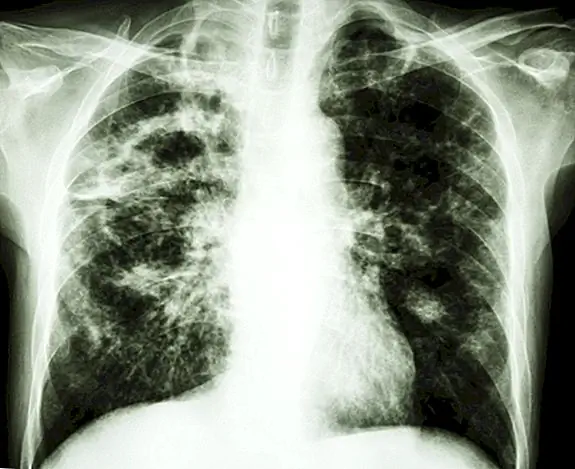

Слово «туберкулез» было придумано Иоганном Лукасом Шонле в 1839 году, от латинского «туберкулеза», что означает «маленький, отек или шип». Однако до 1882 года, когда д-р Роберт Кох обнаружил туберкулезную палочку, за что он получил Нобелевскую премию в 1905 году, что название «туберкулез» стало использоваться исключительно для обозначения болезни, ранее широко известной как потребление.

Итак, почему был выбран «phthisis» или «потребление» для названия? Это объяснялось тем, что болезнь, казалось, потребляла человека, и их вес резко снижался по мере прогрессирования заболевания.

• Хотя многие сегодня в развитых странах считают, что туберкулез ушел в прошлое, это совсем не так. В мире насчитывается более восьми миллионов новых случаев заражения людей туберкулезом каждый год, из которых около двух миллионов человек умирают от этой болезни.